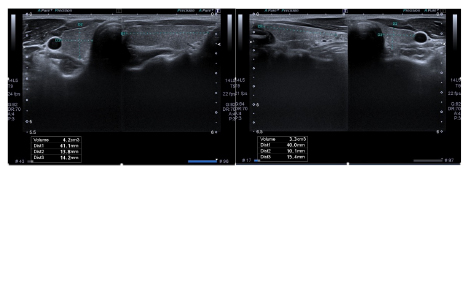

• Ultrasound-based thyroid volume of Cambodian adults

Sruy Huy, M.D., Vanthy VAR, M.D., Ponndara Ith, M.D., Chanvohreak Hang, M.D., Prorpey Khim, M.D., Kimsour Kuch, M.D., Rathana Kea, M.D., Chhuong Uy, M.D., Chinsorn Khut, M.D.

23-32